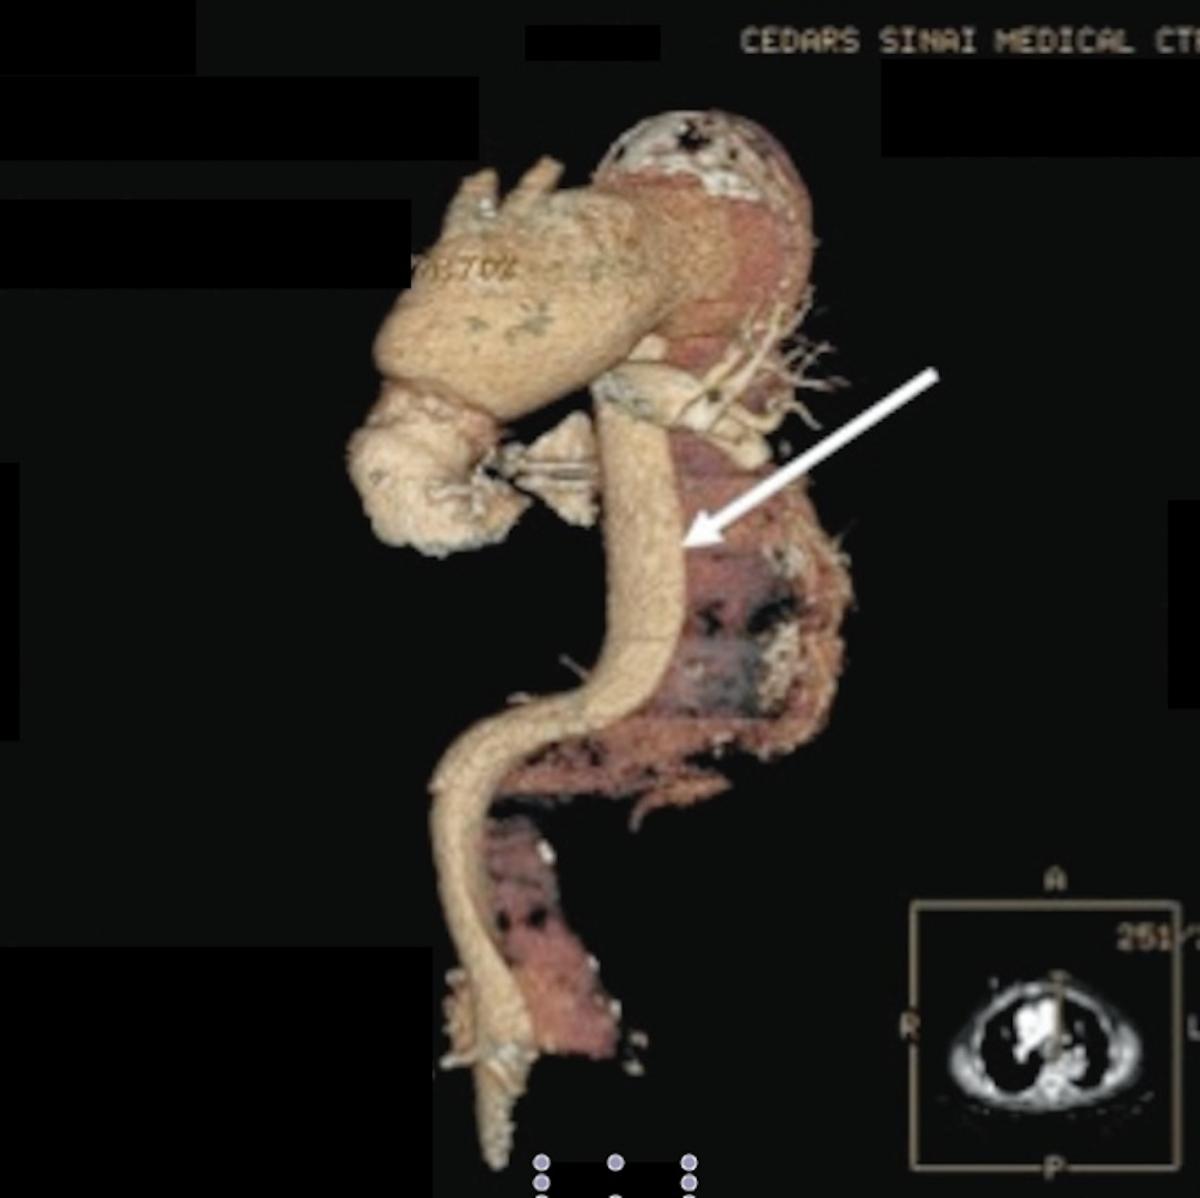

The operative aims for this complex patient were the following: replacing remainder ½ of the ascending aorta, repair of remaining pseudoaneurysm perfusing the posterior Bentall graft (Figure 1C), total arch replacement, and exclusion of false lumen in descending thoracic aorta. It was clear that this operation had to obviate further sternotomies. Therefore, a two-stage hybrid procedure was planned with an open surgical part replacing the ascending and transverse aorta and an endovascular approach to complete the elephant trunk in the descending thoracic aorta. The patient had uneventful forth redo-sternotomy and extensive lysis of adhesions. Deep hypothermic circulatory arrest was initiated with antegrade cerebral perfusion through right axillary artery perfusion. The aortic arch was opened and resected. The left carotid artery was used for bilateral antegrade cerebral perfusion, while the left subclavian artery was clamped to reduce steal phenomenon (Figure 4A). The elephant trunk cuff was placed in the proximal descending aorta after a generous surgical fenestration of the septum. Using a 30mm Dacron graft, the distal aortic anastomosis was performed about a cm distal to left subclavian artery and perfusion to lower extremity was initiated through a second arterial cannula and a side-branch. While rewarming the patient, a trifurcated graft was anastomosed to all brachiocephalic vessels (Figure 4B). The ascending pseudoaneurysm was repaired by cutting out the old Dacron graft down to neo-sinotubular junction. Next the trifucated graft was anastomosed to the ascending aorta and the patient was weaned uneventfully off the heart-lung machine. The circulatory arrest time to lower body was 52 minutes, while the operative time was eight hours. The patient was extubated, neurologically intact, next day in the intensive care unit. His postoperative course was complicated by hospital-acquired pneumonia and C. difficile colitis. Due to infection risk, it was decided not to perform the endovascular stage in the same hospital stay, therefore six weeks after his initial operation, he returned for the TEVAR.

Figure 3: 3-D reconstruction of the thoracoabdominal aorta with the true lumen (arrow) and the chronic dissection.